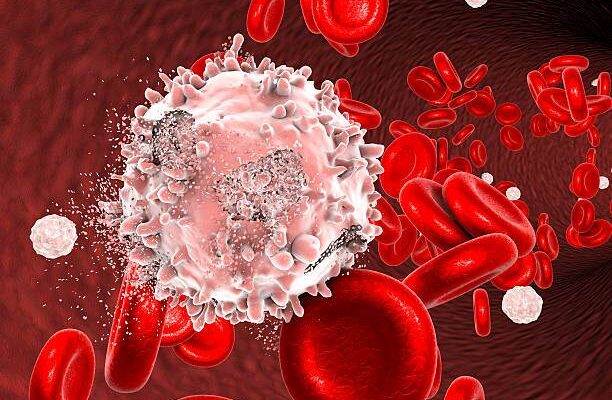

Lösemi; hastalığın ilerleyiş seyrine ve bozulmaya uğramış kan hücresinin türüne göre kronik lösemi ve akut lösemi şeklinde ikiye ayrılmaktadır. Bu genel ayrım da kendi içinde dallara ayrılmaktadır.

Akut lösemi; ağır belirtileri bir anda ortaya çıkan, vücutta hızlı bir şekilde ilerleyip birkaç gün ya da birkaç hafta gibi kısa sürede 4. evre ile karşı karşıya bırakan lösemi çeşididir. Akut lösemi kendi arasında ikiye ayrılır:

Kemik iliğinde üretilen lökositlerden (beyaz kan hücrelerinden) olan lenfositlerin, henüz olgunlaşmamış olan haline lenfoblast denir. Bu lenfoblastların olgunlaşamaması ve bu olgunlaşmamış hücrelerin kontrolsüz bir şekilde çoğalıp kana geçmesi ise kan değerlerini bozarak akut lenfoblastik lösemi‘yi oluşturur.

Kemik iliğinde üretilen lökositlerden (beyaz kan hücrelerinden) olan granülosit ve monositlern henüz olgunlaşmamış haline blast adı verilir. Bu işlev görmeyen genç hücreler aşama aşama olgunlaşır ve bağışıklığa katkı sağlar. Ancak bazı durumlarda bu genç hücreler olgunlaşamaz ve çok kontrolsüz bir şekilde üreyip kanda birikim yapar. Bu da akut miyeloid lösemi‘yi oluşturur.

Kronik lösemi ise çok geniş bir zaman yayılabilen yavaş ve sinsi bir şekilde ilerleyen lösemi çeşididir. Zaman içerisinde pek çok kişinin dikkate almayacağı belirtiler yaşatır. Hafif yorgunluklar, iştahsızlık gibi çok da dikkate alınmayan basit semptomlar belki de kronik löseminin habercisi olabilir. Ne kadar hızlı ilerleyeceği kişinin bünyesine, yaşam tarzına ve çevresinde bulunan etkenlere göre değişiklik gösterebilir. Genellikle rutin kan testlerinde tesadüfen rastlanır. (Bu şekilde erken evrede yakalanabilmesi mümkündür.) Kronik lösemi de kendi arasında iki gruba ayrılır:

Beyaz kan hücresi de denilebilen lökositlerin, lenfosit isimli alt tipinde meydana gelen mutasyondan dolayı oluşan kanserleşmeyi ifade eder. (kronik lenfositer lösemi hakkında daha fazla detay için kronik lenfositer lösemi yazısına göz atabilirsiniz.)

Lenfosit, granülosit ve monositerden oluşan lökositlerin (beyaz kan hücrelerinin) granülosit tipinde meydana gelen kanserleşmeyi ifade eder. Kanserleşmiş granülositler kontrolsüz bir şekilde ürer ve kanda birikim yapar. Ayrıca bu durum, kanda pıhtılaşmayı sağlayan trombositlerin de sayısını arttırır. Daha fazla detay için Kronik miyeloid lösemi yazısına bakabilirsiniz.